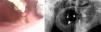

Los pacientes fueron seguidos clínica y radiológicamente, mediante ortopantomografía (OPG) o tomografía computarizada cada 3 meses o ante cualquier eventualidad clínica durante 2 años. Durante el seguimiento se valoró la curación ósea (definida como la desaparición de la exposición ósea sin clínica asociada y mejoría confirmada radiológicamente), la disminución o aumento de la exposición ósea, la aparición de episodios infecciosos-inflamatorios agudos, la duración de los episodios y la presencia de otras complicaciones asociadas.

Los pacientes en estadio 3 fueron tratados en todos los casos con mandibulectomía segmentaria. Tres de ellos fueron reconstruidos con colgajo microquirúrgico de peroné (fig. 4 a-c), y uno con barra mandibular más cierre directo. Fueron tratados mediante secuestrectomía 7 pacientes, de los cuales 5 tenían estadio 2 y 2 estadio 1. Con desbridamiento local solo fue tratado un paciente que presentaba estadio 1. El tratamiento conservador se aplicó al resto de los pacientes en estadio 1 (4 pacientes) y a 3 pacientes del estadio 2.

Estadio 3. (4 casos). El paciente tratado con mandibulectomía segmentaria y barra de titanio presentó una infección a los 8 meses que obligó a retirarla. Tres meses después se volvió a fijar con otra barra, que no presentaba más complicaciones tras 24 meses. Los otros 3 pacientes tratados con mandibulectomía segmentaria y reconstrucción con colgajo de peroné evolucionaron satisfactoriamente. Dos de ellos fueron rehabilitados con implantes dentales 6 meses después. El otro usa prótesis removible. Ninguno ha registrado complicaciones al cabo de 12 meses.